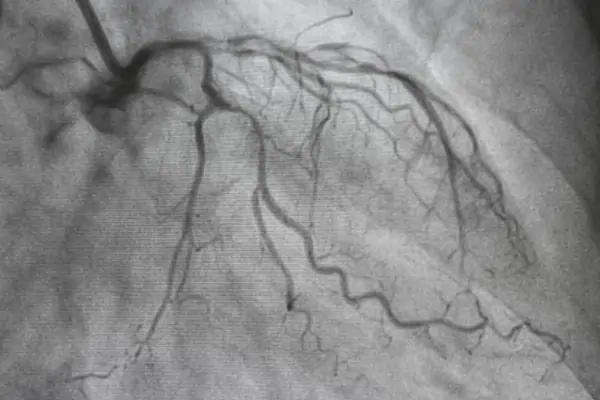

After the severity of the disease has been determined through diagnostic tests like a Coronary Angiogram, CABG is recommended in cases where medication or coronary angioplasty isn’t feasible. Typically, it is the last line of intervention. A CABG is conducted by taking a healthy blood vessel from another part of the body — typically the legs, arms, chest or wrist — to make a new pathway for the flow of blood and oxygen to the heart — essentially bypassing the old, blocked pathway. This new pathway is called a graft.

The most important test in understanding blockage placement and coronary anatomy is the coronary angiography. The angiography helps determine a SYNTAX score, which in turn helps doctors decide between PCI and CABG. An echocardiogram measures ejection fraction and ventricular function. ECG detects arrhythmia and ischemia. Blood tests check other markers like glucose and lipid levels, kidney and liver function, coagulation and CRP levels.